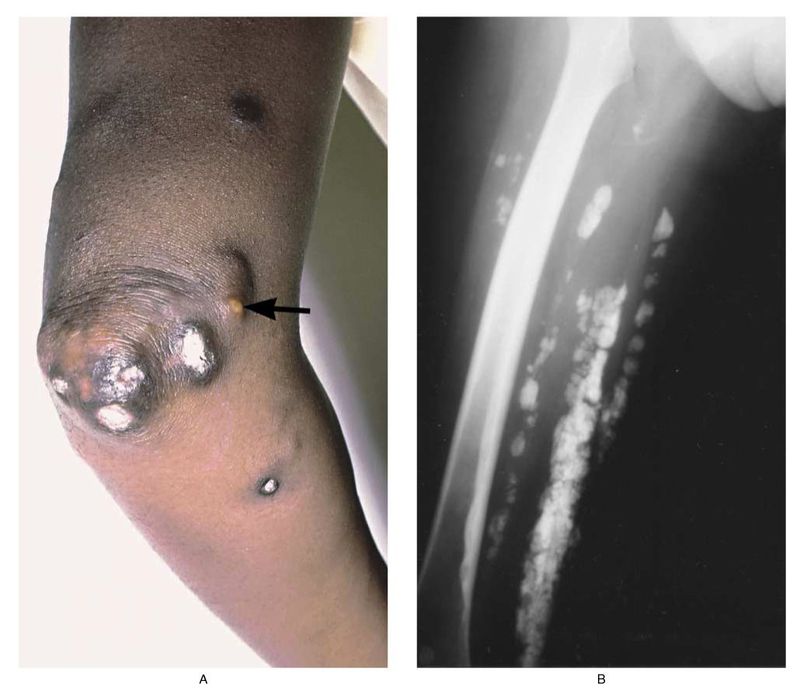

The elbow (Panel A) of a 33-year-old woman who had had dermatomyositis since childhood shows subcutaneous calcifications extruding through the skin. A focus of purulent inflammation within a calcium deposit is evident (arrow). An x-ray film of the patient's thigh (Panel B) shows calcifications beneath the skin and within the muscle tissue. Some lesions on the skin in this area were palpable, and others were not visible. Deposition of calcium continued in this patient despite therapy with prednisone, azathioprine, and diphosphonates. Marinos C. Dalakas, M.D. National Institute of Neurological Disorders and Stroke, Bethesda, Source: nejm.org